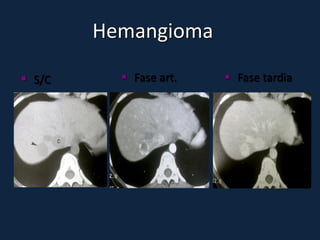

Hemangioma

► s/c: Lesões bem definidas, lobuladas, hipodensas ao parênquima e

isodensas aos vasos intra-hepáticos.

► c/c: (aspecto típico em lesões 2-10cm):

 Fase arterial: Realce periférico nodular e descontínuo, com áreas

nodulares ou globuliforme, da periferia para o centro da lesão. Centrípeto.

 Fase portal: Realce progressivo e centrípeto (da periferia para o centro).

 Fase tardia: Ocorre o preenchimento completo e homogêneo da lesão, com

realce persistente.

► Tempo de enchimento completo depende do tamanho da lesão

► Lesões pequenas (<2cm): enchimento completo rápido

► Lesões grandes (>10cm): preenchimento incompleto da lesão (presença

de trombos, áreas de fibrose e/ou necrose).

 S/C      Fase art.    Fase tardia